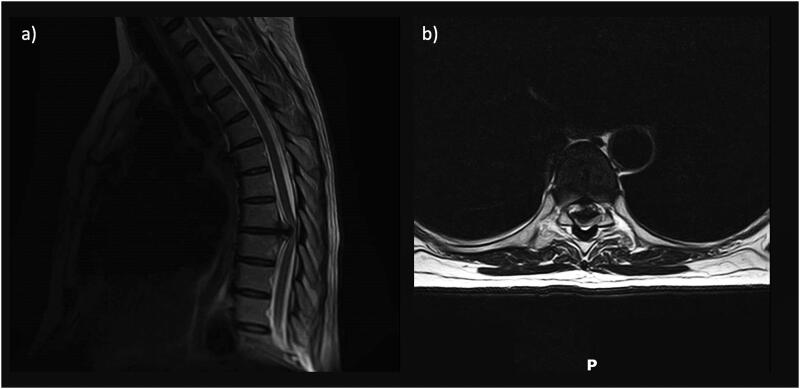

目的:脊髓脑脊液(CSF)漏是一种常见病,其治疗方法多种多样。对于高流量漏,许多研究都主张进行硬脑膜修复和 CSF 分流。LiquoGuard7® 可以自动、精确地控制压力和容量,并计算患者特定的 CSF 产出率 (prCSF):本单中心病例系列包括接受复杂脊柱手术的患者,这些患者的情况如下:1) 预计术中和/或术后会出现高流量 CSF 渗漏;2) 使用 LiquoGuard7® 进行腰椎 CSF 引流。为每位患者量身定制了 CSF 引流方案,并结合分层脊柱伤口闭合术:结果:共纳入三名患者,病理类型各异:结果:共收治了三名患者,他们患有不同的病症:T7/T8 椎间盘脱出、T8-T9 脑膜瘤和 T4-T5 转移性脊髓压迫。前两名患者接受了 CSF 转移术,以防止术后 CSF 渗漏,而第三名患者则因术后 CSF 渗漏而需要接受 CSF 转移术。所有病例的 CSF 都明显分泌过多(平均 >/=140 毫升/小时)。根据患者的具体情况制定脑脊液引流方案后,没有病例因脑脊液瘘修补(包括胸腔积液)、伤口破裂或感染而需要进一步干预:结论:患者特异性脑脊液引流可能是治疗复杂脊柱手术中术中和术后高流量脑脊液漏的有效工具。这些系统可减少术后从伤口或邻近体腔漏出的 CSF。需要进一步开展更大规模的研究,以评估这种方法的比较效益和成本效益。

Results: Three patients were included, with a variety of pathologies: T7/T8 disc prolapse, T8-T9 meningioma, and T4-T5 metastatic spinal cord compression. The first two patients underwent CSF diversion to prevent post-op CSF leak, whilst the third required this in response to post-op CSF leak. CSF hyperproduction was evident in all cases (mean >/=140ml/hr). With patient-specific CSF diversion regimes, no cases required further intervention for CSF fistulae repair (including for pleural CSF effusion), wound breakdown or infection.